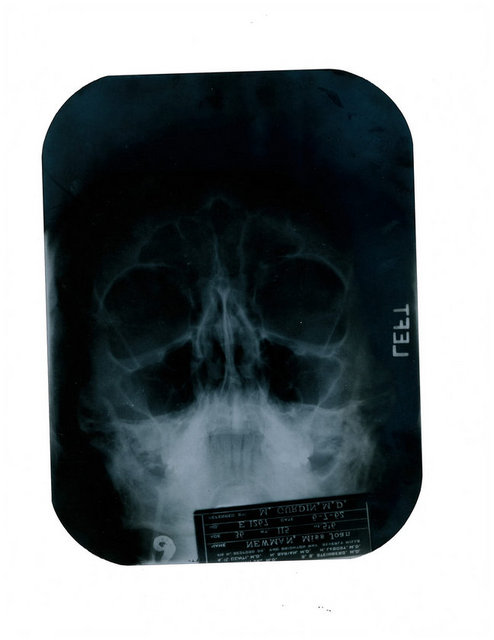

Sinemanın efsane sarışını Marilyn Monroe'nun geçirdiği estetik operasyonları belgeleyen röntgen filmleri ve doktorların birbirleriyle yazışmaları California'da yapılacak bir açık artırmada satışa sunuluyor